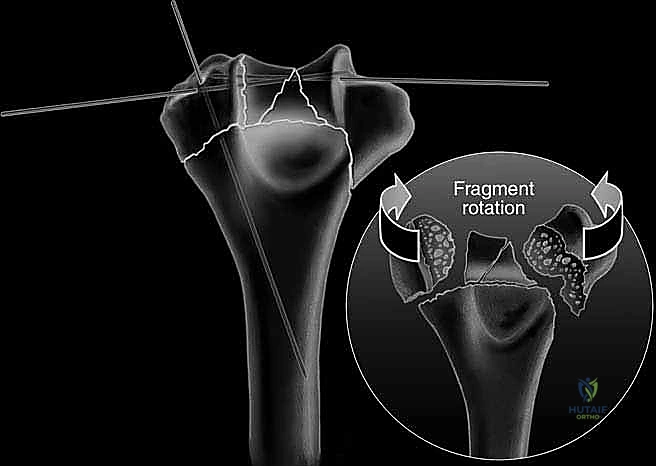

The classification of these fractures is primarily dictated by the AO/OTA alphanumeric system, which categorizes distal humerus fractures into type 13-A (extra-articular), 13-B (partial articular), and 13-C (complete articular). The 13-C fractures—specifically the C2 and C3 subtypes—are the focus of this text, characterized by complete dissociation of the articular block from the diaphyseal shaft, coupled with varying degrees of articular and metaphyseal comminution. The "spool" shape of the trochlea and the hemispherical capitellum must be anatomically reconstructed to restore the complex hinge-and-pivot kinematics of the ulnohumeral and radiocapitellar joints. Failure to recognize the extent of coronal shear components or profound metaphyseal bone loss during the initial evaluation will inevitably lead to catastrophic intraoperative difficulties and subsequent construct failure.

The fracture reduction sequence follows a strict "inside-out" and "bottom-up" philosophy. The primary objective is the anatomical restoration of the articular block (the "tie"). The trochlear and capitellar fragments are meticulously debrided of hematoma, reduced using pointed reduction forceps, and provisionally stabilized with smooth Kirschner wires. This articular assembly is then definitively fixed using headless compression screws or countersunk cortical lag screws, ensuring no hardware violates the joint surface. Once the articular block is reconstituted into a single, solid unit, it is reduced to the medial and lateral columns of the humeral diaphysis. Provisional fixation to the shaft is achieved with K-wires, and orthogonal fluoroscopy is utilized to confirm anatomical alignment, particularly the crucial 30-degree anterior tilt of the articular surface.